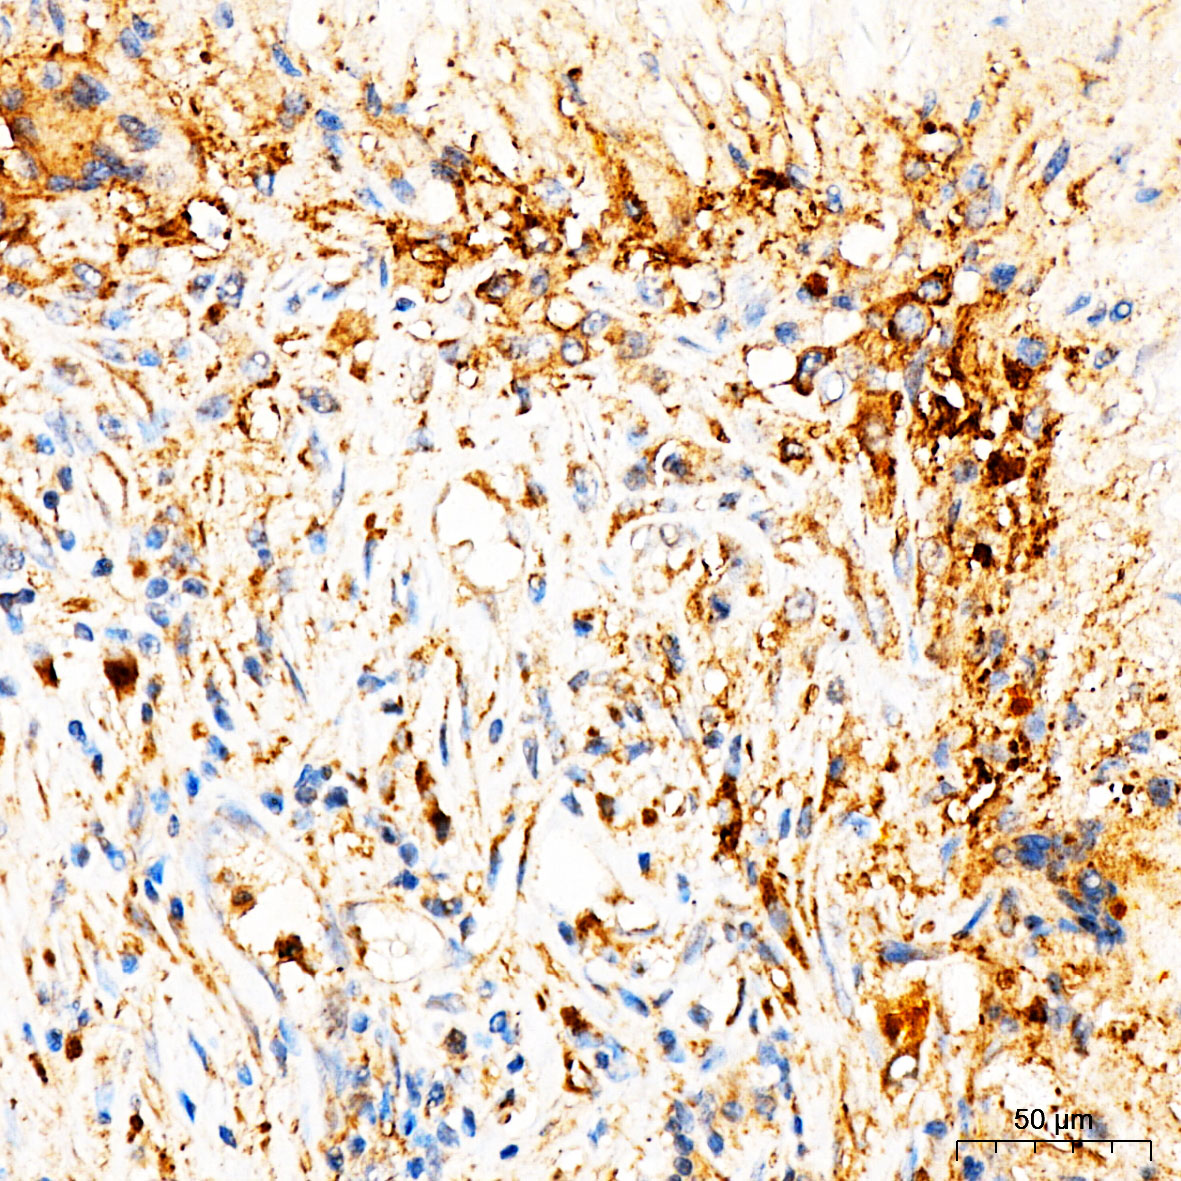

| Immunohistochemistry analysis of paraffin-embedded Human liver cancer tissue using [KD Validated] MRPL27 Rabbit pAb (A25221) at a dilution of 1:100 (40x lens). High pressure antigen retrieval was performed with 0.01 M citrate buffer (pH 6.0) prior to IHC staining. |